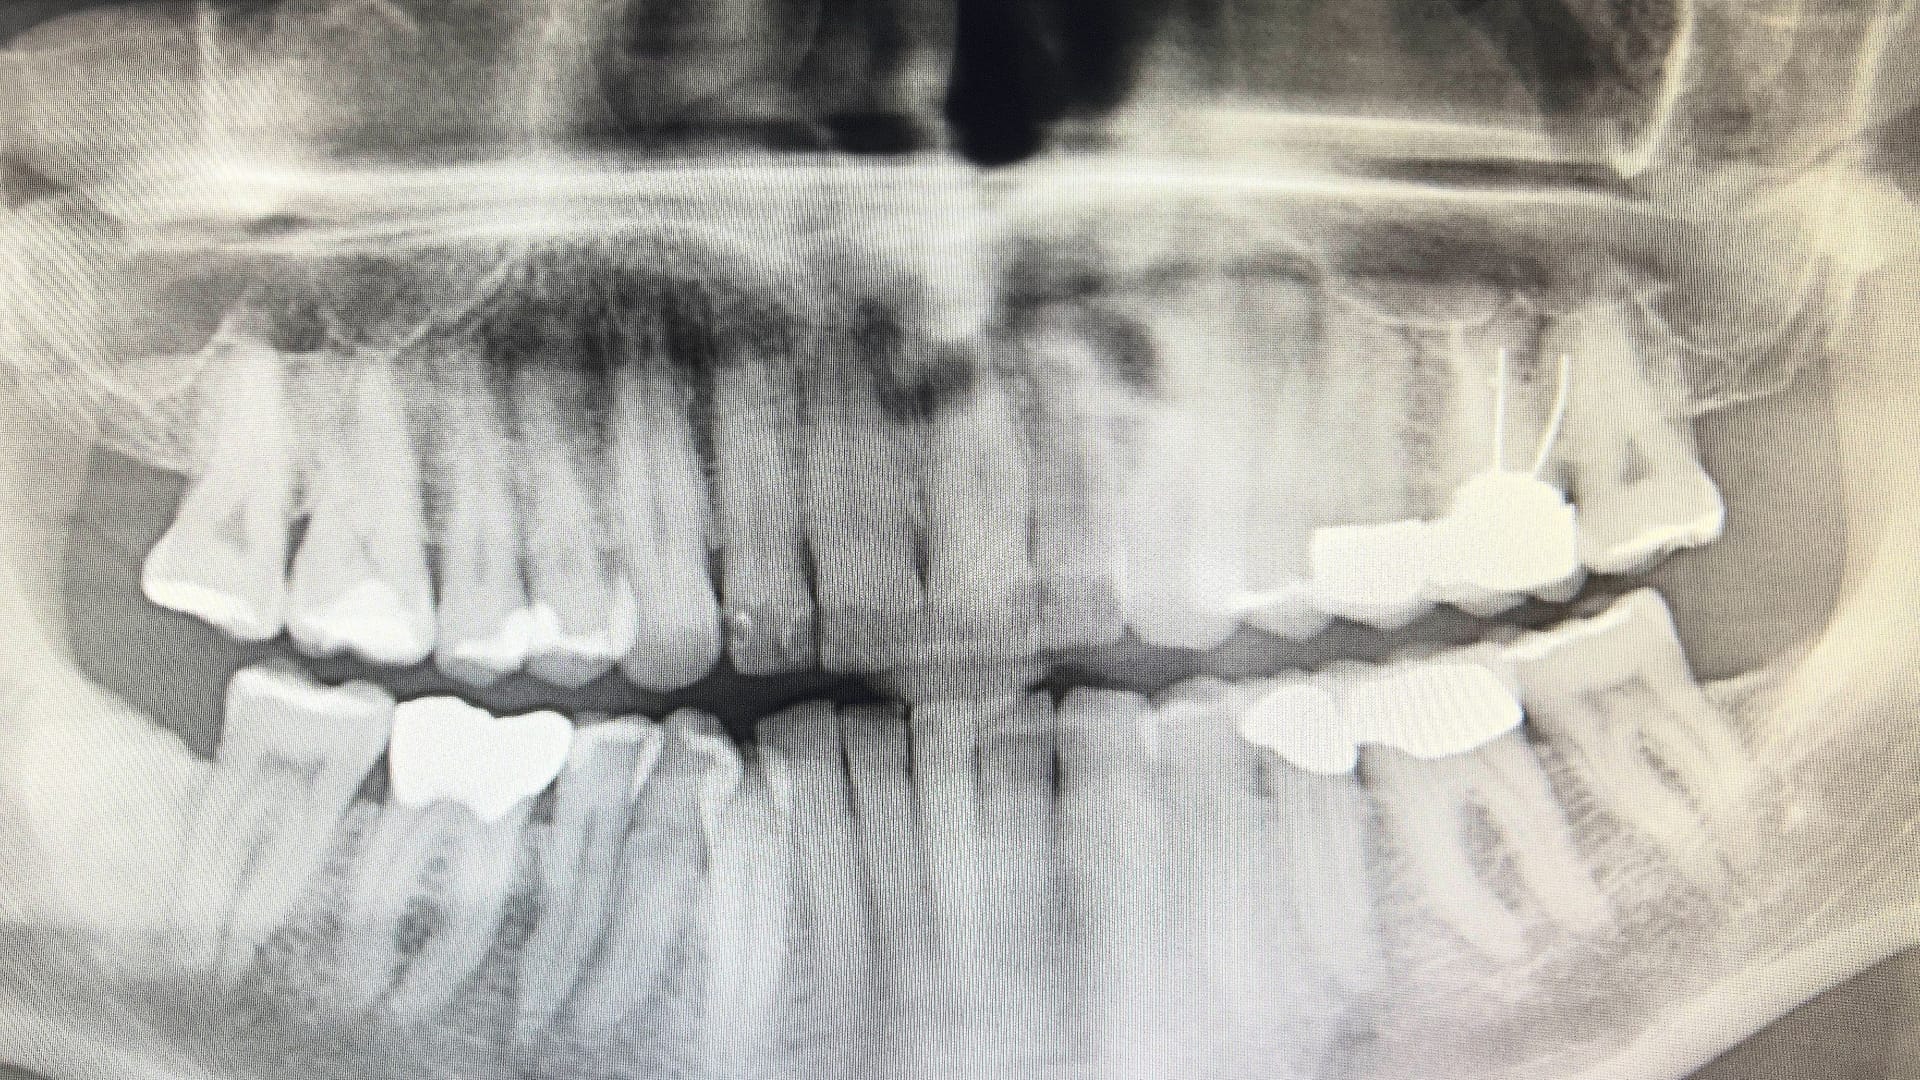

Am Montag hat am Landgericht Nürnberg-Fürth der Prozess gegen einen Zahnarzt aus München begonnen. Der 60 Jahre alte Mann hat laut Anklageschrift einen Schaden von mehr als drei Millionen Euro angerichtet. Dieses Geld soll er nach dem Willen der Staatsanwaltschaft jetzt zurückzahlen.

Die anklagende Behörde ist die bei der Generalstaatsanwaltschaft Nürnberg angesiedelte Bayerische Zentralstelle zur Bekämpfung von Betrug und Korruption im Gesundheitswesen (ZKG). Der Vorwurf lautet auf gewerbsmäßigen Betrug: Im Zeitraum von Januar 2015 bis Januar 2021 soll der Arzt insgesamt 25 Quartalsabrechnungen manipuliert haben.

Er habe fiktive Leistungen für gesetzlich versicherte Patienten abgerechnet, schreibt die Generalstaatsanwaltschaft. Die Patienten seien häufig nur einmal wegen einer Notfallbehandlung in der Praxis des Arztes gewesen. Gegenüber der Kassenzahnärztlichen Vereinigung Bayern habe er aber auch noch weitere, in Wahrheit nie erbrachte Leistungen in Rechnung gestellt.

Dazu soll er persönlich die Versichertenkarten der Patienten eingelesen haben. Dabei habe er die Karten auch für zurückliegende und für in der Zukunft liegende Quartale erfasst, indem er das Datum am Computer verstellt habe. Auch bei eigenen Praxisangehörigen sowie deren Angehörigen habe der Mann auf diese Weise Abrechnungsbetrug begangen, teilte die Generalstaatsanwaltschaft mit.